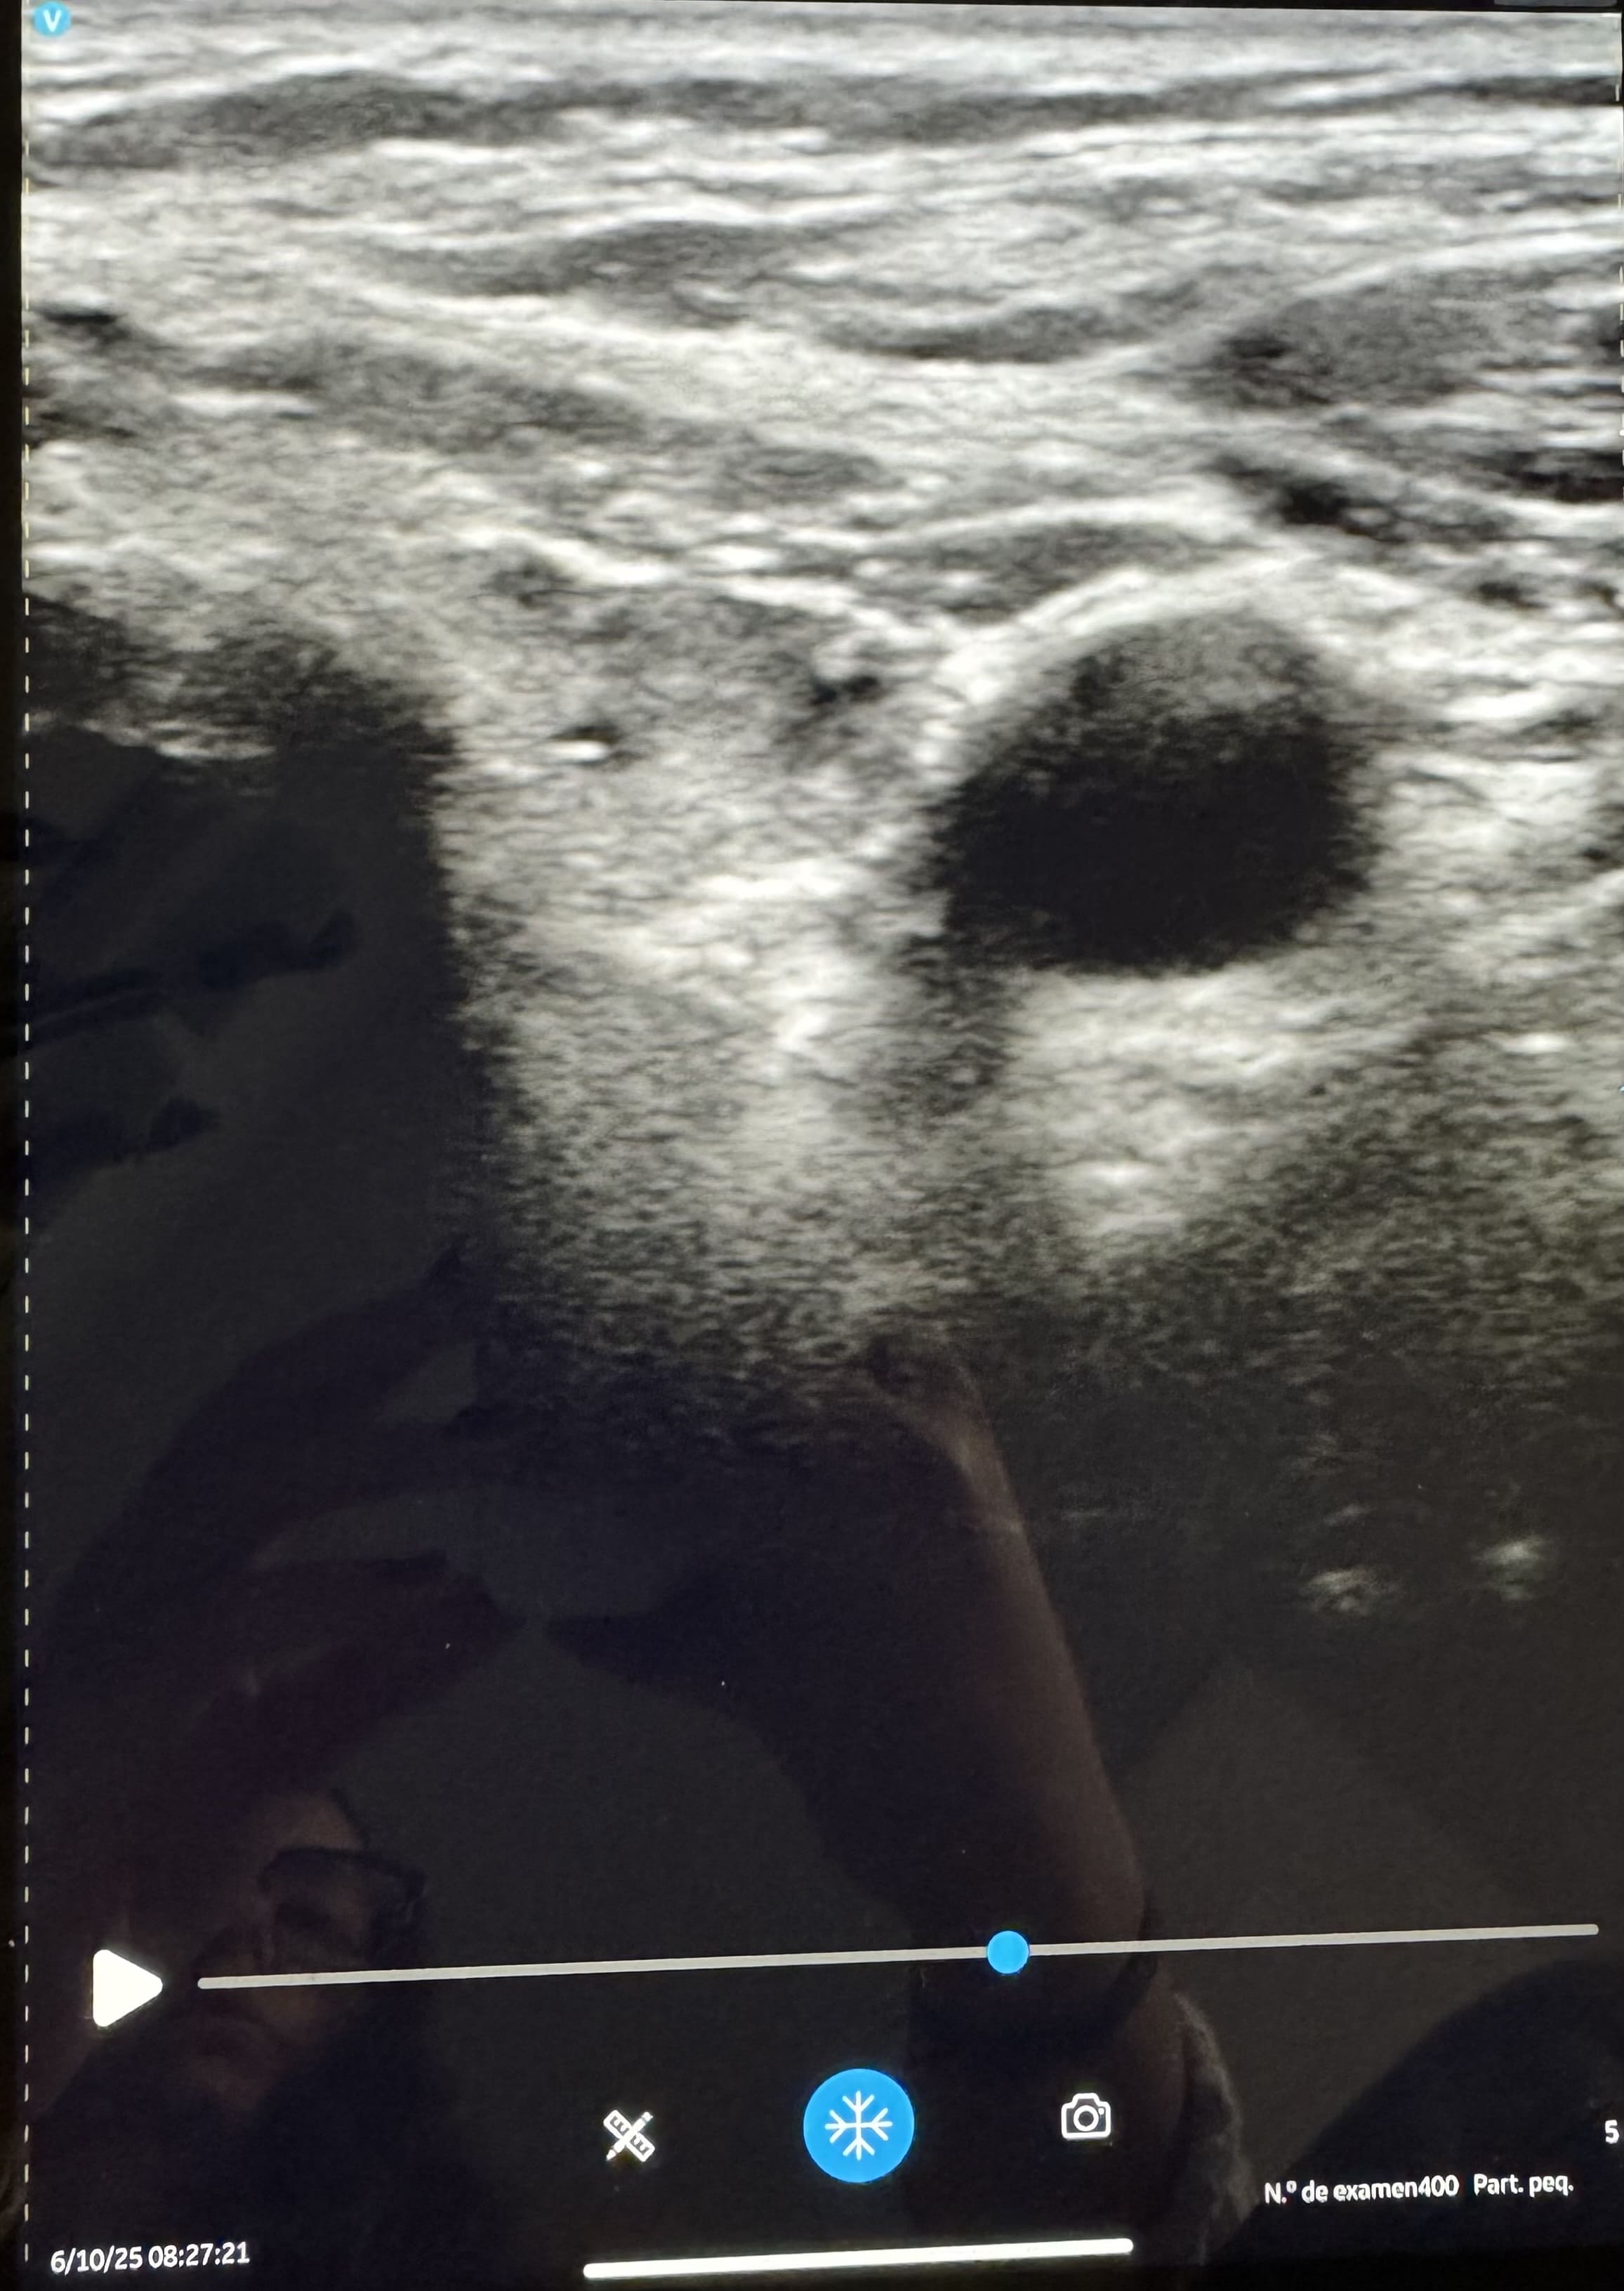

En ecografía realizada en el centro de salud se aprecia tiroides moderadamente aumentado de tamaño, estructura homogénea y con varios nódulos en ambos lóbulos, destacando uno de ellos en lóbulo tiroideo derecho de consistencia mixta e irregular, con algunas calcificaciones en su interior y siendo más ancho de alto 1*7x1.5, apreciándose vascularización periférica.

Tras la realización de la ecografía clínica, se solicita de forma reglada donde describen un tiroides aumentado de tamaño, con nódulos sólidos y homogéneos con escasa vascularización, en probable relación con bocio multinodular. Describen además un nódulo de mayor tamaño en lóbulo derecho de unos 15 mm y con vascularización periférica y componente exofítico, clasificándolo de TIRADS 5, recomendándose así PAAF.